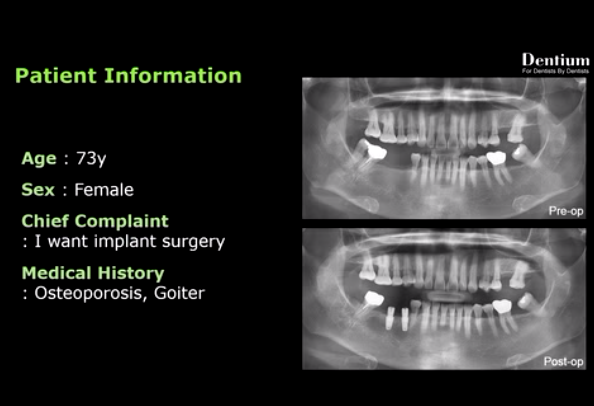

Buccal contour augmentation using OSTEON™ ll Collagen (Short)